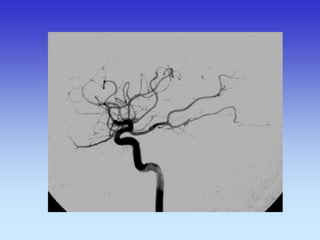

METODE PRIKAZA KRVNIH ŽILA

•UZ-DOPPLER

•DSA

•CTA

•MRA

B-mod i obojeni Doppler karotidne arterije

VASKULARNA OPSKRBA WILLIS-ijev prsten